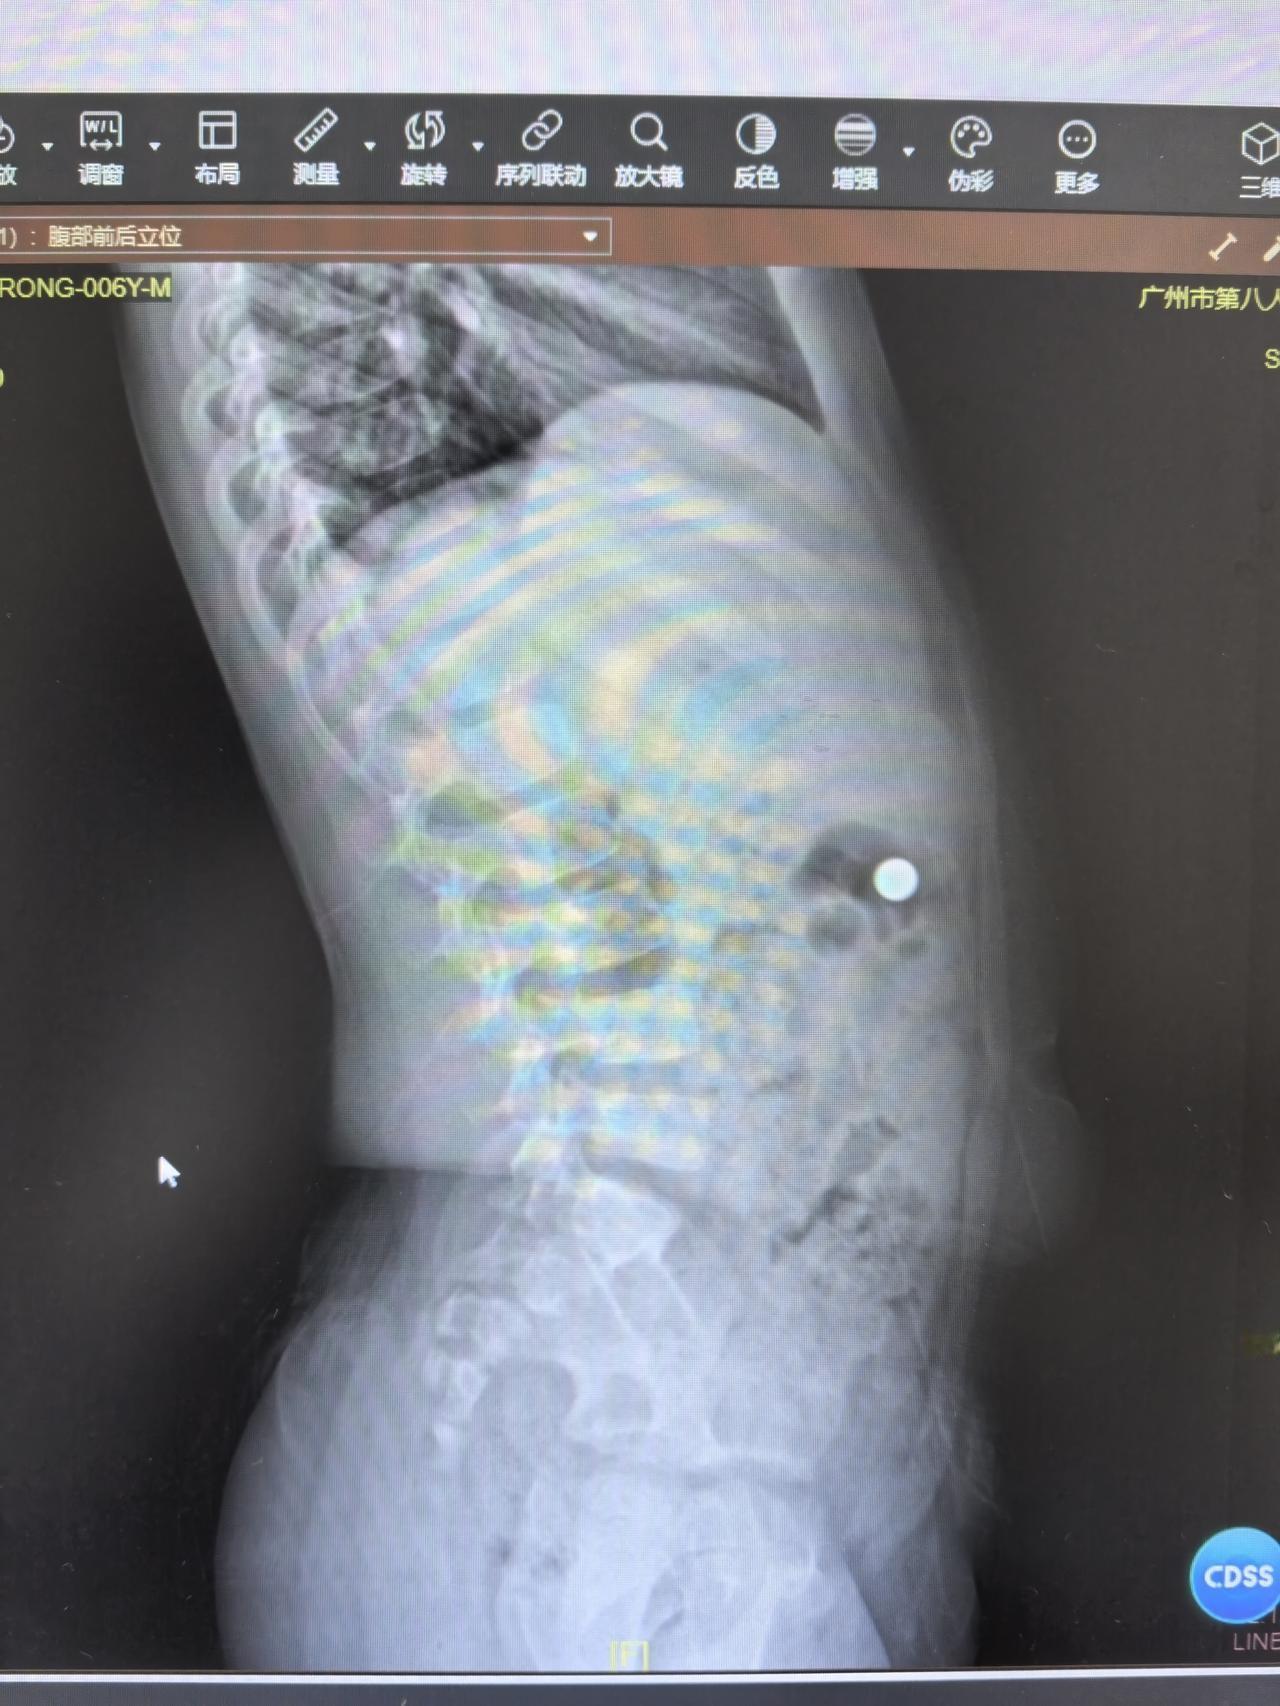

你们猜猜 这个小家伙 把什么吃到肚子里去了?